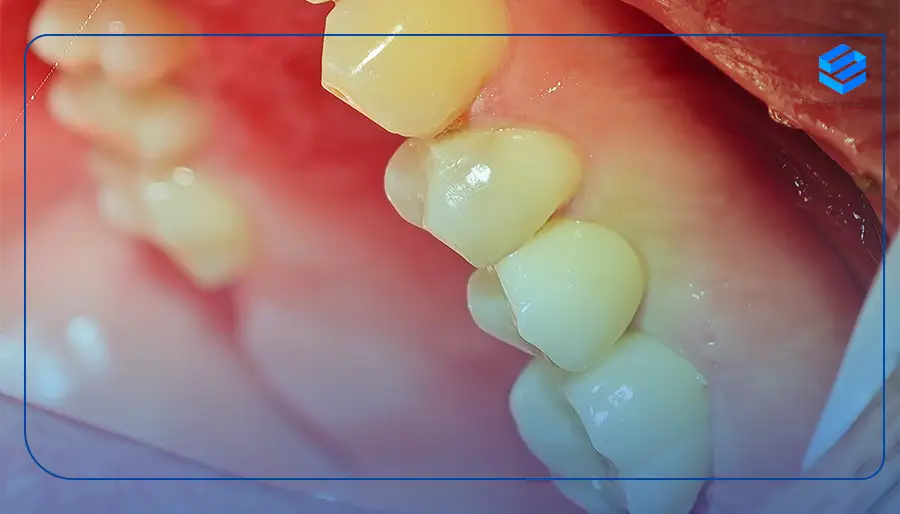

دندان نیش یک دندان تک ریشهای است و شرایط درمان آن با ایمپلنت دندانهای آسیاب متفاوت است. برای کاشت ایمپلنت دندان نیش بالا و پایین بهتر است تا ۱۸ سالگی صبر کرد و از آنجایی که دندانهای نیش نقش زیادی در زیبایی ظاهر دارند، باید با دقت کامل و از ایمپلنت مناسب و ظریف برای آنها استفاده شود.